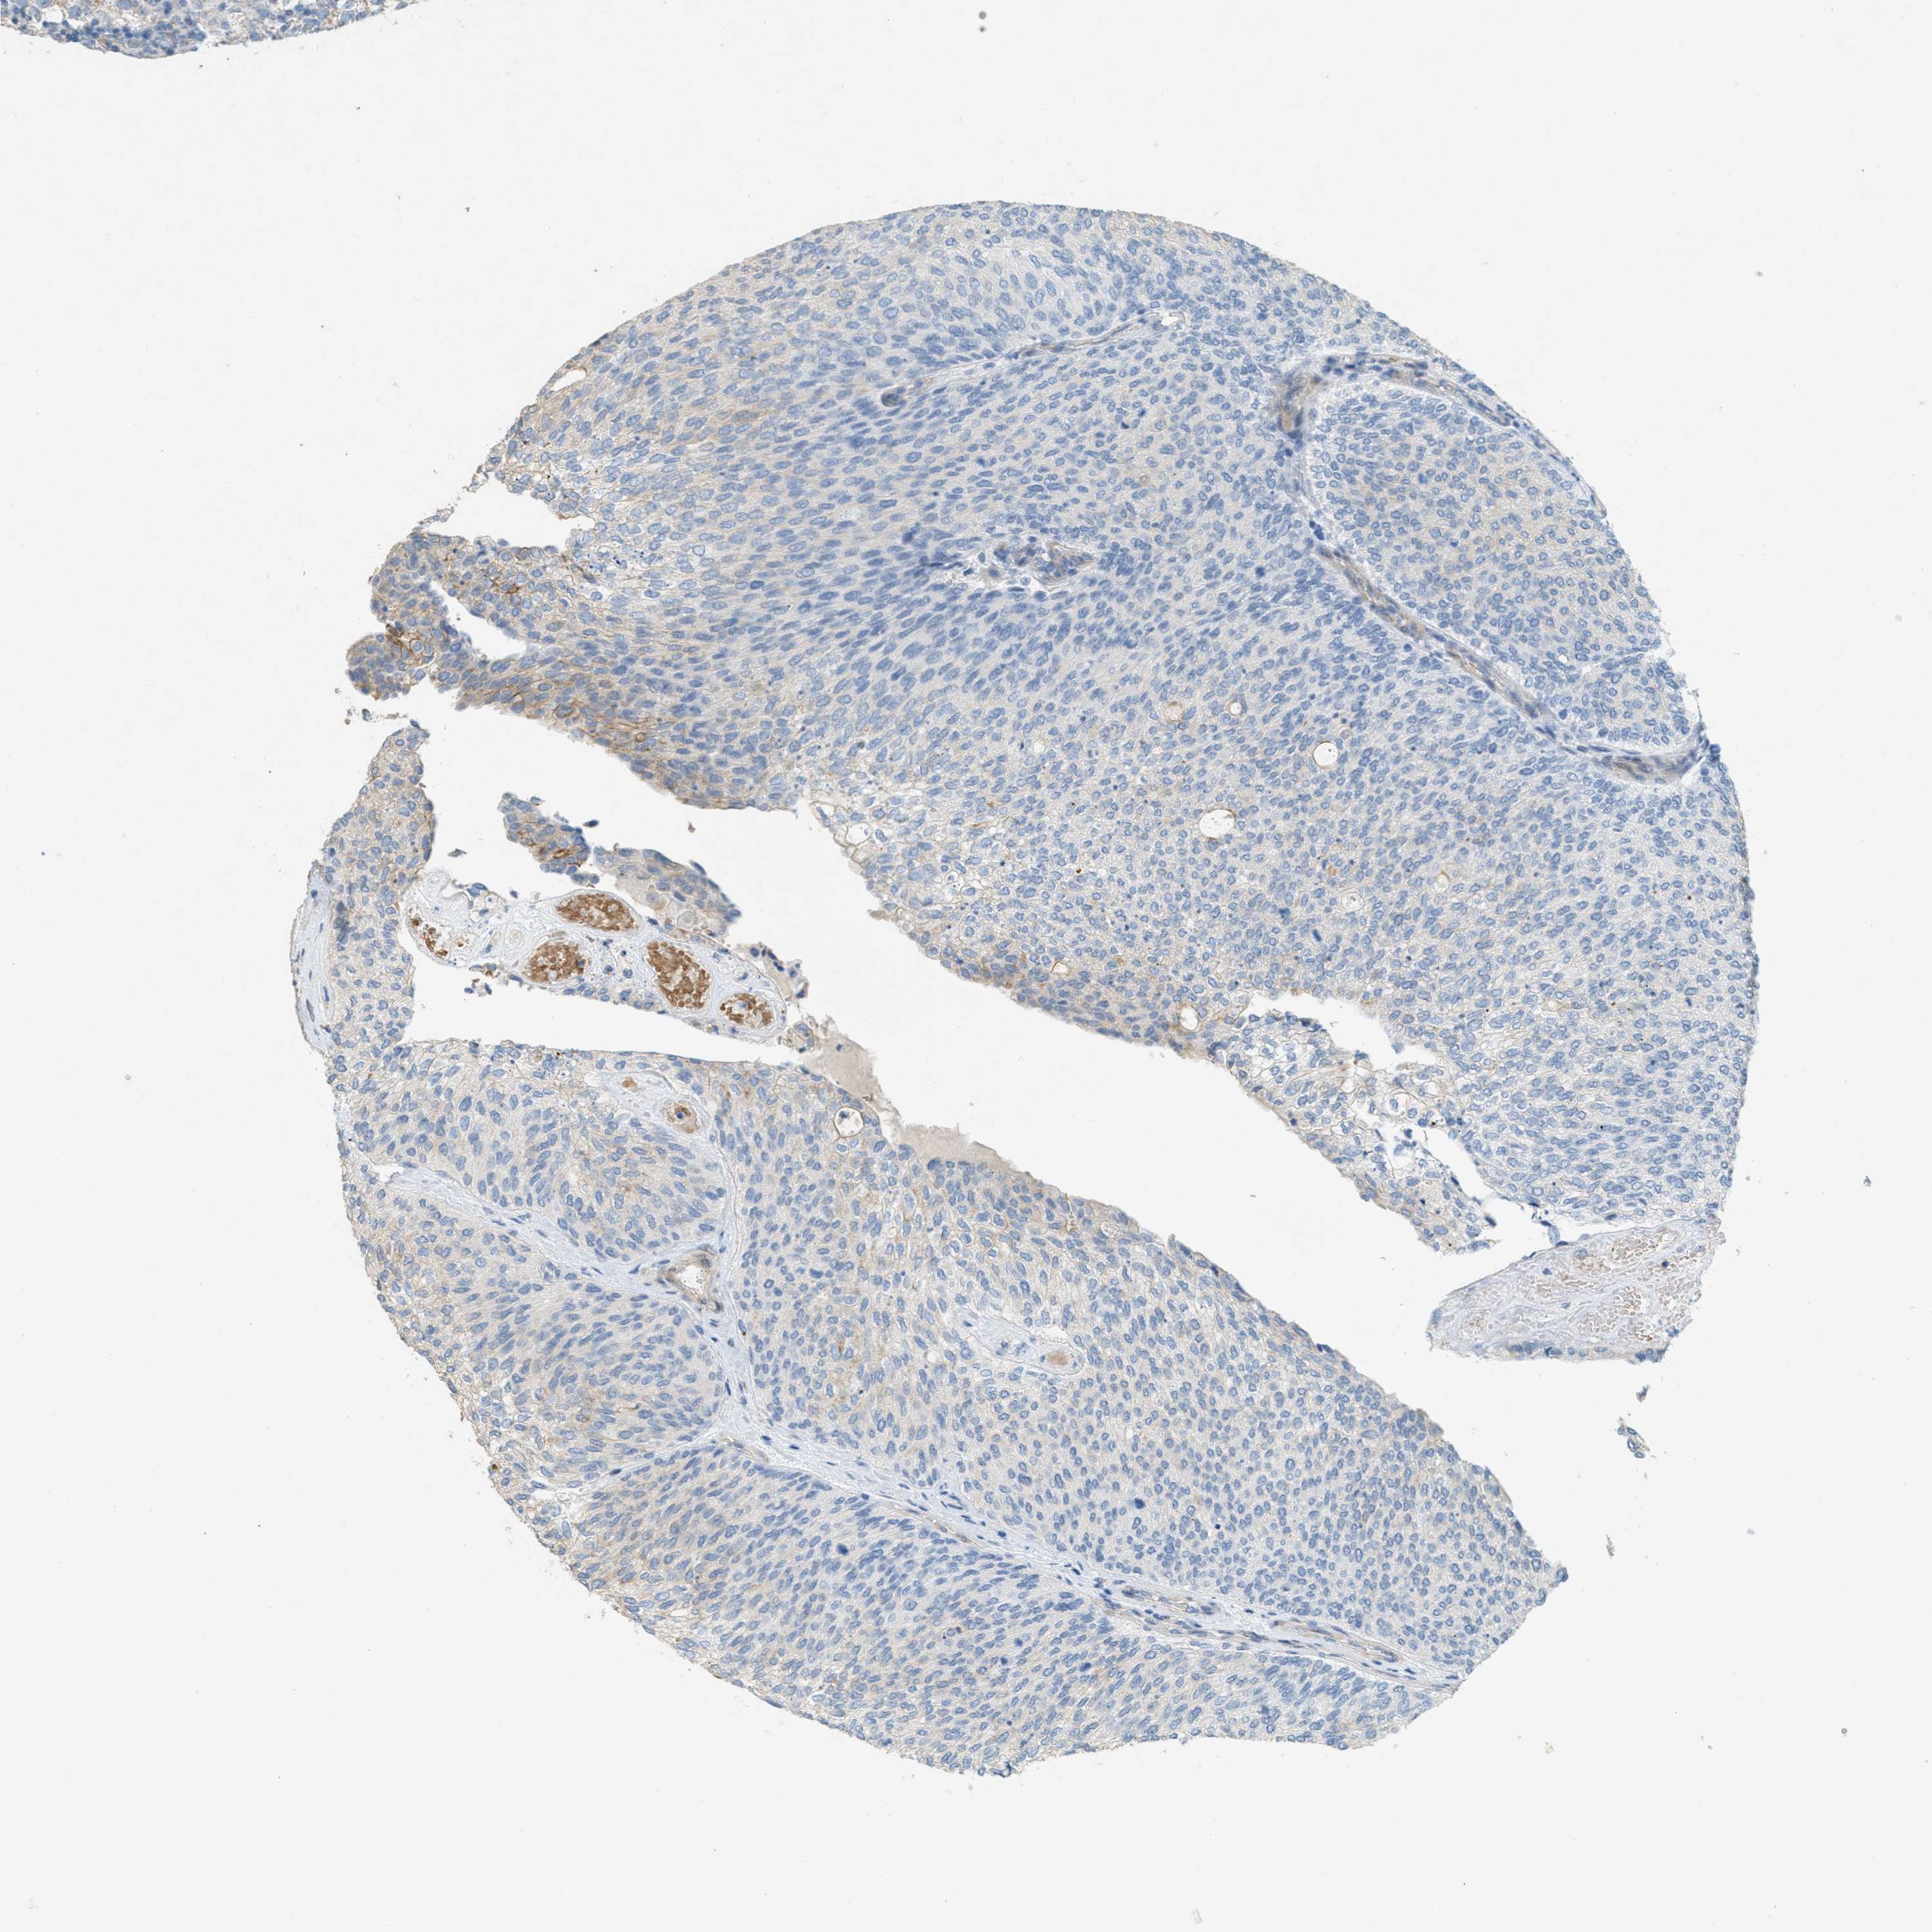

UROTHELIAL CANCER - Protein expressioni

A mouse-over function shows sample information and annotation data. Click on an image to view it in a full screen mode. Samples can be filtered based on level of antibody staining by selecting one or several of the following categories: high, medium, low and not detected. The assay and annotation is described here.

Note that samples used for immunohistochemistry by the Human Protein Atlas do not correspond to samples in the TCGA dataset.

Antibody stainingi

Antibody staining in the annotated cell types in the current human tissue is reported as not detected, low, medium, or high, based on conventional immunohistochemistry profiling in selected tissues. This score is based on the combination of the staining intensity and fraction of stained cells.

Each image is clickable and will lead to virtual microscopy that enables deeper exploration of all samples and also displays staining intensity scores, fraction scores and subcellular localization as well as patient and tissue information for each sample.

Antibody HPA017642

Staining

High

Medium

Low

Not detected

Intensity

Strong

Moderate

Weak

Negative

Quantity

>75%

75%-25%

<25%

None

Location

Nuclear

Cytoplasmic/membranous

Cytoplasmic/membranous,nuclear

Urothelial carcinoma, Low grade

Urothelial carcinoma, High grade